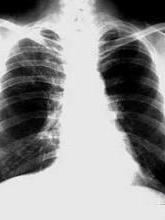

肺真菌病,是真菌(霉菌)所引起的肺病。从流行病学调查发现人体的真菌感染很多个别地区组织胞质菌、球孢子菌的感染率可高达50%以上,但大多数为亚临床型在短时间内未被发现即自愈。